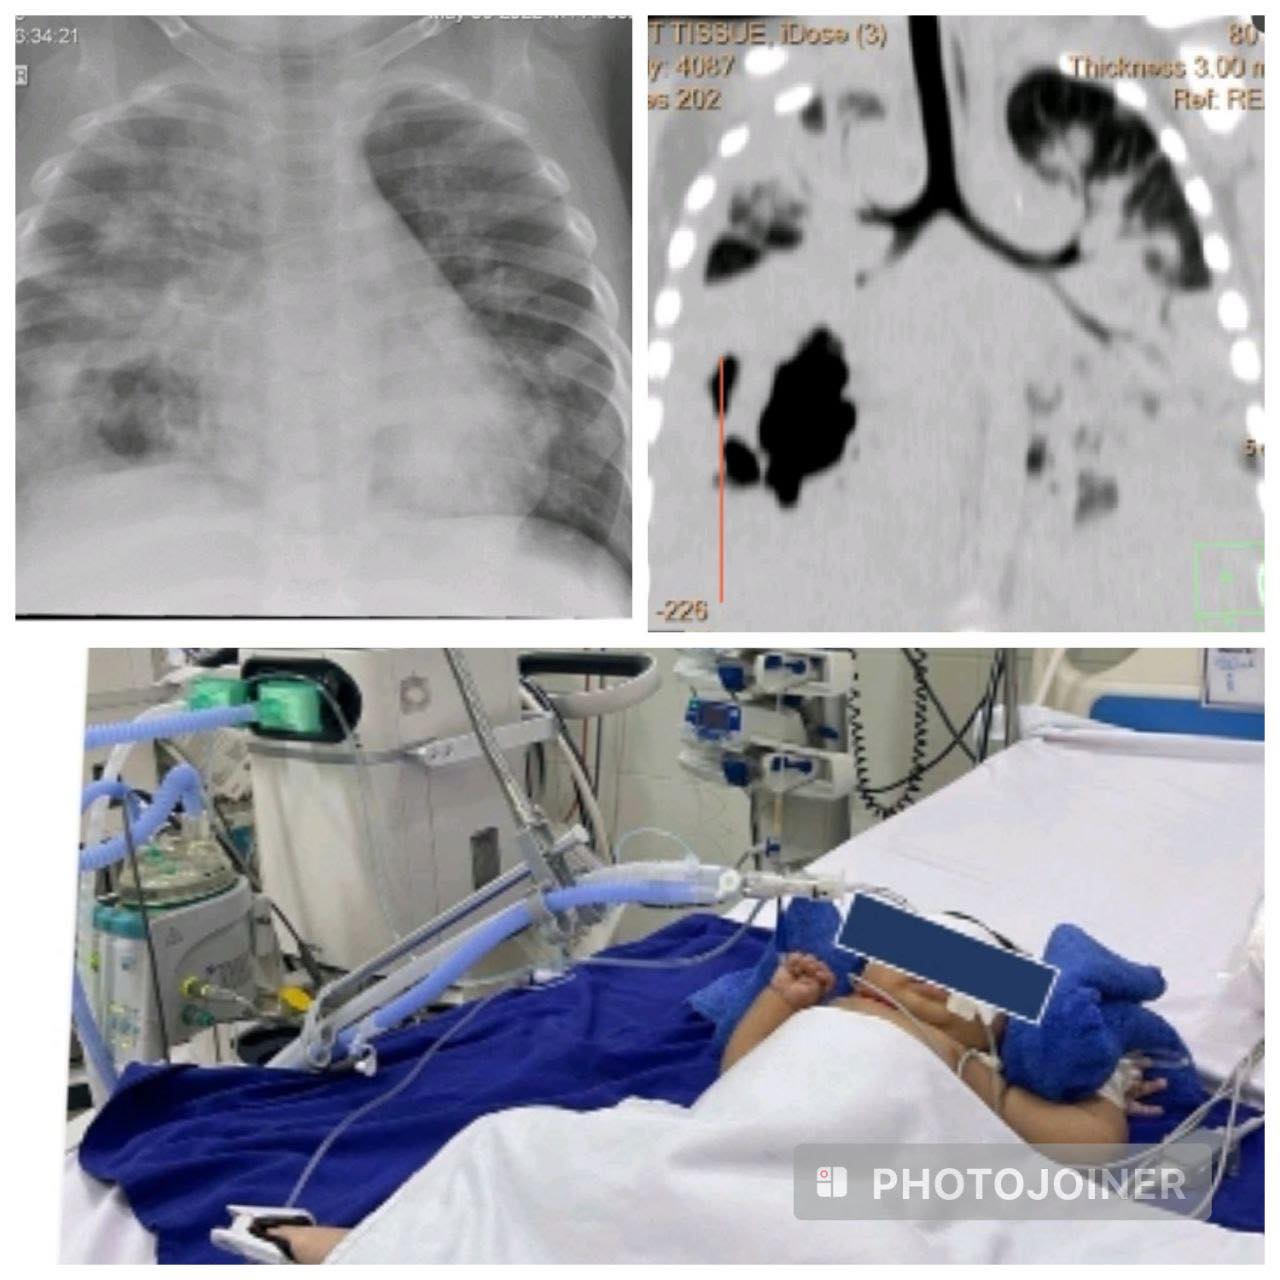

តាមរយៈខ្លឹមសារបង្ហោះរបស់ Dr. Beat Richner បានបញ្ជាក់ថា៖« ក្មេងប្រុសតូចម្នាក់នេះ អាយុ១២ខែ មកពីខេត្តកណ្តាល យកមកមន្ទីរពេទ្យគន្ធបុប្ផានាដង្ហើមចុងក្រោយ និងស្ថិតក្នុងស្ថានភាពធ្ងន់ធ្ងរបំផុត មានជំងឺរលាកសួតទាំងសងខាងយ៉ាងធ្ងន់ធ្ងរនិងវិវត្តទៅជាដំបៅខ្ទុះធ្លុះធ្លាយសួតយ៉ាងស្មុគស្មាញបំផុត ដោយសារមេរោគបាក់តេរីកាចឈ្មោះ Burkholderia pseudomallei + វីរុសRSV+ វីរុស enfluenza A រួមគ្នាវាយប្រហារសួតក្មេងប្រុសតូចនេះ។ ក្មេងប្រុស ត្រូវបានជួយសង្រ្គោះជីវិតនៅផ្នែកសង្រ្គោះបន្ទាន់គន្ធបុប្ផាភ្នំពេញ អស់រយៈពេល ៦៤ថ្ងៃ ដោយជំនួយម៉ាស៊ីនសប់ដង្ហើម និងត្រូវបានធ្វើការវះកាត់យកក្លែបសួតស្អុយរលួយចំនួន ២លើក ថ្ងៃនេះបានជាសះស្បើយ និងមានសុខភាពល្អវិញហើយ។»